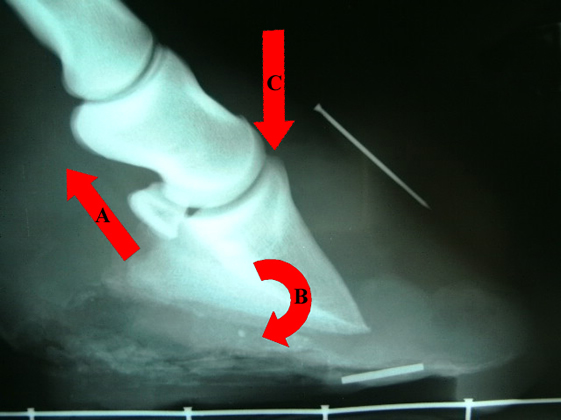

Most of the strength of the laminae attaching the hoof wall to the bone column is concentrated around the front of the hoof wall and this is the area that weakens most during laminitis. The tendons at the back of the foot tend to pull the bone within the foot downwards and towards the rear (ie: rotate it). In addition the rear of the foot bone is supported by the frog so the front end naturally ‘tips’ downwards. As the laminae weaken, the bone in the foot rotates and the tip of the bone then presses down on the sole, crushing the sensitive tissue there and causing more pain. Levels of rotation can vary from zero in mild attacks to 15-20% of rotation in the most severe cases. X-rays are critical for monitoring levels of rotation – there is no way of telling how much rotation has occurred without them. Above is an x-ray of a severe case of laminitis. The laminae have weakened and slipped and the pull of the tendons (A) has caused the bone to rotate (B). In addition some sinkage (C) has occurred. Note the wide divergence between the hoof wall (marked by the nail) and the bone.